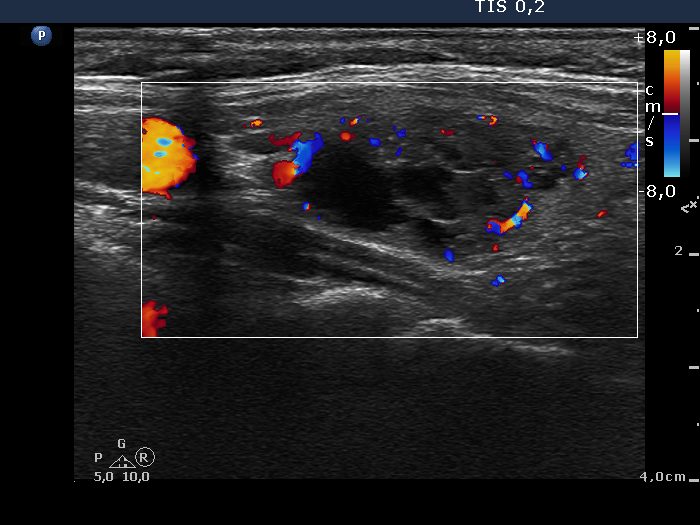

Follow-up examination one year later (ultrasonographic picture 6)

Left lobe, longitudinal view, color Doppler mode. The nodular area presents a lobulated surface caused by the presence of mutliple discrete lesions.